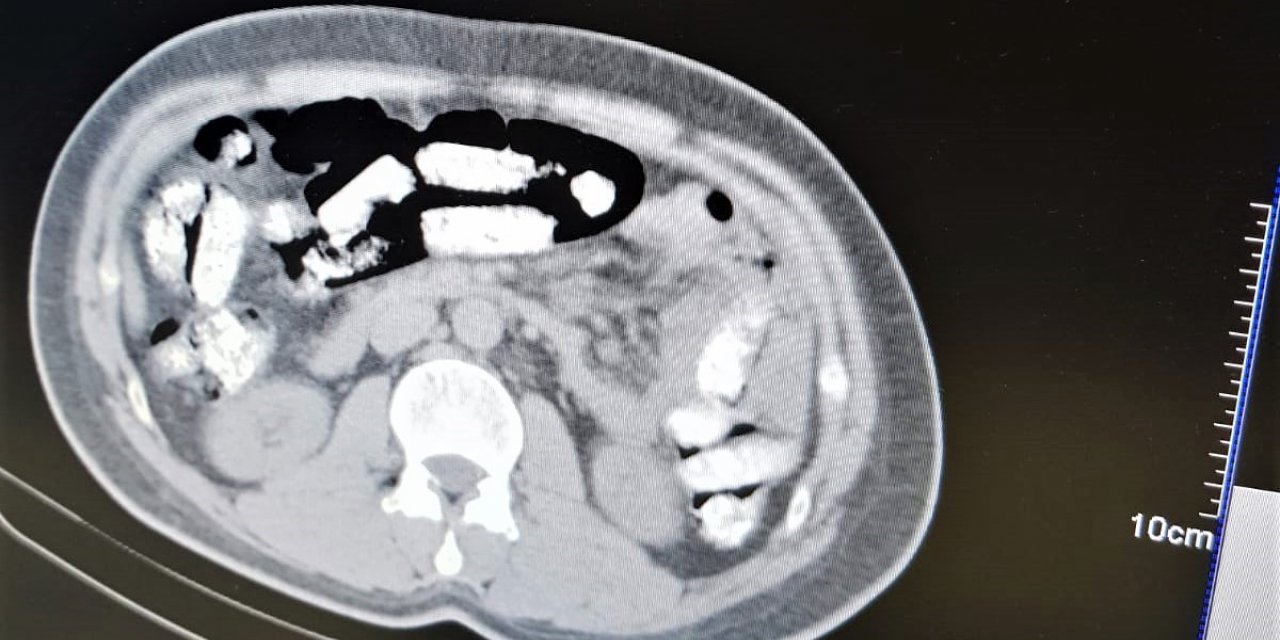

Midesinde uyuşturucu sevkiyatı yapan zanlı tutuklandı